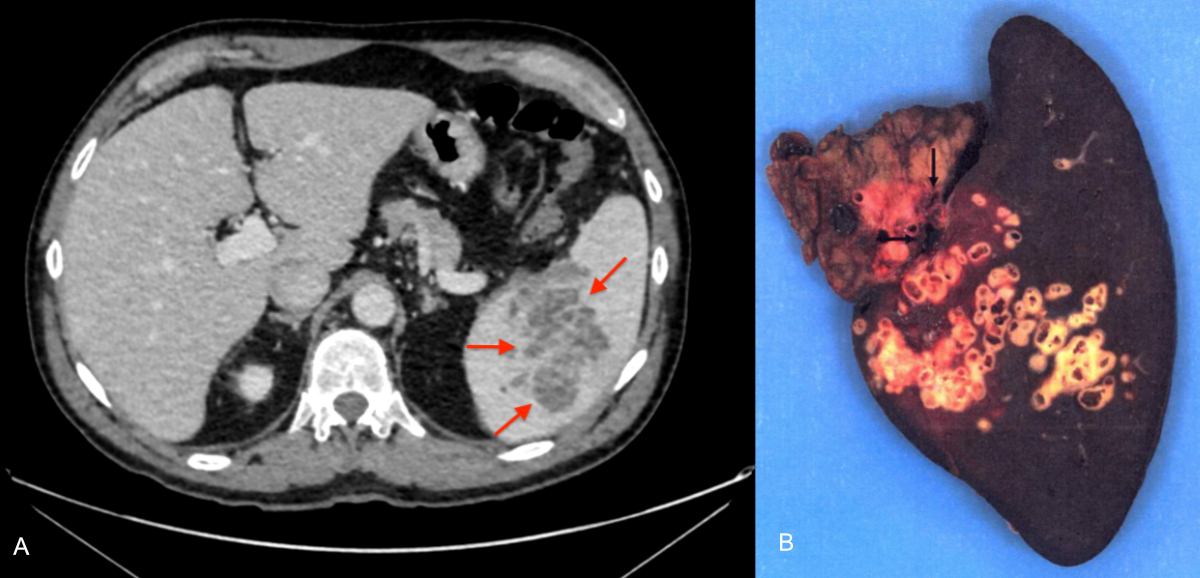

Figure 5A–B: 67-year-old patient admitted to the emergency department for a painful crisis in the left hypochondrium occurring 4 years after superior mesenteric vein thrombosis. A: Contrast-enhanced CT scan, portal phase, axial cut. Multicystic hypodense splenic lesion (arrows). B: Total splenectomy specimen, macroscopic view. The lesion is filled with multiple alveoli (arrows) characteristic of alveolar echinococcosis, corresponding to parasitic microcysts. No clear limits.

The analysis of the surgical specimen confirmed the diagnosis of alveolar echinococcosis in 12 of the 13 patients for whom we had access to the histopathological report. For 1 patient, who died, we were unable to retrieve the report. One patient underwent surgery with an initial diagnosis of very probable cholangiocarcinoma. Histopathological examination of the surgical specimen, followed by specific serology, led to the diagnosis of alveolar echinococcosis. The patient with primary splenic alveolar echinococcosis underwent curative splenectomy (figure 5).

We report only one primary extrahepatic form (4%) as a splenic location. This result is consistent with those of a large European series (n = 599) [30] and a French series (n = 387) [25], reporting respectively 2% and 4% primary extrahepatic locations, including the spleen. The patient described in our series had a history of superior mesenteric vein thrombosis following laparoscopic resection of the caecum performed 4 years before the diagnosis of splenic alveolar echinococcosis. The mesenteric venous thrombosis likely facilitated redirection of blood flow towards the splenic vein, thereby allowing the primary infection of the spleen by the parasite. A case of primary vertebral alveolar echinococcosis in a patient with liver cirrhosis complicated by portal hypertension has recently been reported, probably involving the same mechanism of portal flow diversion [31].